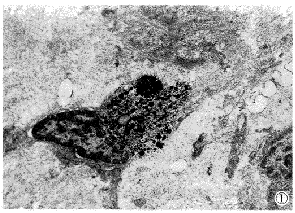

透视电镜注射普通SPIO组,电子致密影(SPIO颗粒)仅出现在kupffer细胞内,肝细胞内未见有SPIO粒子分布(图1);而注射LAC-HSA-SPIO组,电子致密SPIO除出现在kupffer细胞外,还广泛存在于肝细胞膜上及肝细胞膜内(图2),证实LAC-HSA-SPIO受肝细胞膜ASG受体的介导,二者结合后随胞吞作用进入了肝细胞内。

图1 Kupffer细胞内可见大量电子致密的SPIO粒子。

图2 肝细胞内证实有较多电子致密的SPIO粒子,提示LAC-HSA-SPIO受肝细胞膜ASG受体的介导而进入肝细胞内。